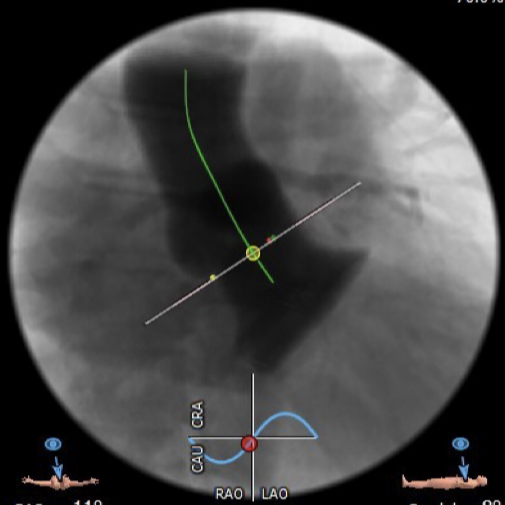

在放射科,超声科和麻醉科的通力协作下,顺利完成了术前准备,术者团队在术中谨慎建立轨道,根据主动脉根部造影的结果,初步判断释放体位是否合适观察瓣叶活动度、是否合并反流,选择合适的跨瓣体位。瓣膜释放前优先确认猪尾管位置,避免瓣膜在释放过程中脱载。